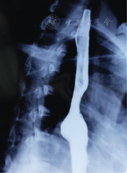

女性,45岁,因"体检发现后纵隔占位6 d"于2015年4月13日入院。查体无明显异常。实验室及器械检查显示:胸部CT显示右后纵隔内可见一较大不规则形异常密度影,最大横断面范围约160 mm×103 mm,内部密度混杂多样,可见多发脂肪成分及钙化灶,见多发分隔及多囊性病灶。增强后病变部分可见强化,部分未见强化,纵隔内心脏、血管、支气管及食管可见明显受压推移改变;纵隔、肺门未见肿大淋巴结影,右侧胸腔可见积液,胸膜未见增厚,考虑畸胎瘤(图1)。心电图示窦性心律,正常心电图。上消化道造影示食管中下段被纵隔右后方块状物推移至左侧;食管黏膜光整,形态规则,蠕动正常(图2)。肺功能检查显示:用力肺活量(forced vital capacity,FVC)为2.21 L,占预计值的77.2%;第1秒用力肺活量(forced vital capacity in the first second,FEV1)为1.79 L,占预计值的74.8%;最大通气量(maximum ventilatory volume,MVV)为86.52 L/min,占预计值的103.2%;FEV1/ FVC%为80.8%,提示肺功能轻度损害,混合性肺通气功能障碍。心脏彩超显示:心脏结构及功能未见明显异常。血常规、肝肾功能、凝血功能、血液传播疾病检查示基本正常。2015年4月20日,患者在双腔气管插管下行静脉复合麻醉,采用右胸后外切口从第6肋上缘进胸,术中见心脏后方巨大囊实性纵隔肿瘤,约18 cm×17 cm×10 cm,占据右后半胸腔。右下肺受压,部分粘连。肿瘤与主动脉、左下肺、右下肺、左右主支气管、食管、膈神经关系紧密,与两侧下肺均有粘连。手术切除完整的具有包膜多结节状肿物(图3)。切面灰白实性,呈鱼肉状,质地中等,界限清。病理诊断:高分化型脂肪肉瘤(图4)。患者病情恢复良好,术后第14天出院。